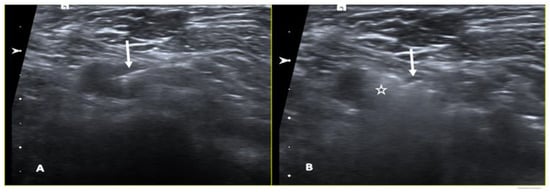

2.6.1. Radioactive Seed Localization

- Diego, E.J.; McAuliffe, P.F.; Soran, A.; McGuire, K.P.; Johnson, R.R.; Bonaventura, M.; Ahrendt, G.M. Axillary Staging After Neoadjuvant Chemotherapy for Breast Cancer: A Pilot Study Combining Sentinel Lymph Node Biopsy with Radioactive Seed Localization of Pre-Treatment Positive Axillary Lymph Nodes. Ann. Surg. Oncol. 2016, 23, 1549–1553. [Google Scholar] [CrossRef] [PubMed]

- Hellingman, D.; Donswijk, M.L.; Winter-Warnars, G.A.O.; de Koekkoek-Doll, P.; Pinas, M.; Budde-van Namen, Y.; Westerga, J.; Vrancken Peeters, M.-J.T.F.D.; Kimmings, N.; Stokkel, M.P.M. Feasibility of Radioguided Occult Lesion Localization of Clip-Marked Lymph Nodes for Tailored Axillary Treatment in Breast Cancer Patients Treated with Neoadjuvant Systemic Therapy. EJNMMI Res. 2019, 9, 94. [Google Scholar] [CrossRef] [PubMed]